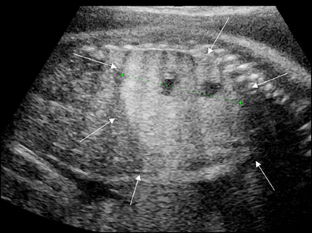

Fig. 3